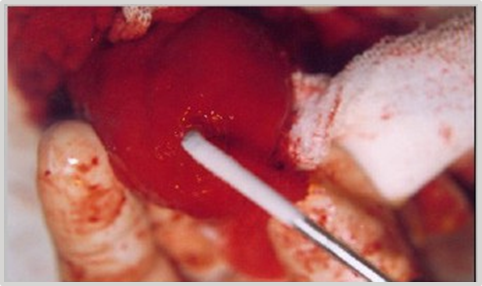

After the laparotomy and cystotomy, the highly vascularized tumor mass is exposed using the "glove finger" maneuver (Figures 3–6). Given the size of the TCC (2.90 cm x 2.50 cm), the entire structure is frozen up to near the base using a short spray tip in a "zig-zag"(a) and then “concentric spiral"(b) movement. The extent of cold is monitored by tactile-visual palpation when the cold line (isotherm at 0°C) approaches to within nearly a millimeter of the mucosal base. Freezing time: 30 seconds (Figure 7) (Figure 8), thawing time: 10 minutes.

Figure 3 Midline laparotomy and exposure of the bladder. Cystotomy.

Figure 4 Exposure of tumor mass.

Figure 5 "Glove Finger" maneuver.

Figure 6 Exteriorization of tumor mass.